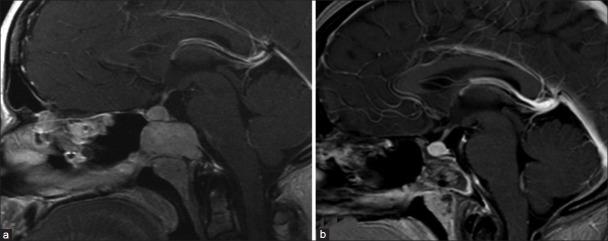

Giant cell reparative granulomas (GCRGs) are rare lesions in the cranial bones. We present a case of this rare lesion emanating from the clivus and replacing the sphenoid sinus, a highly unusual location for this entity.

The case and clinical course of a 29-year-old female who presented with a large sphenoid mass are described here. The patient presented with symptoms of severe headache and diplopia; imaging demonstrated a large sphenoid mass which was completely resected via an endoscopic endonasal approach. It was based on the clivus and was shown to be a GCRG.

巨细胞修复性肉芽肿(GCRGs)是颅骨中罕见的病变。我们报告了一例起源于斜坡并取代蝶窦的这种罕见病变,这一部位对于该病变来说极为罕见。

本文描述了一名29岁女性出现巨大蝶窦肿物的病例及临床过程。患者表现为严重头痛和复视症状;影像学检查显示一个巨大的蝶窦肿物,通过鼻内镜经鼻入路将其完全切除。该肿物起源于斜坡,病理显示为巨细胞修复性肉芽肿。